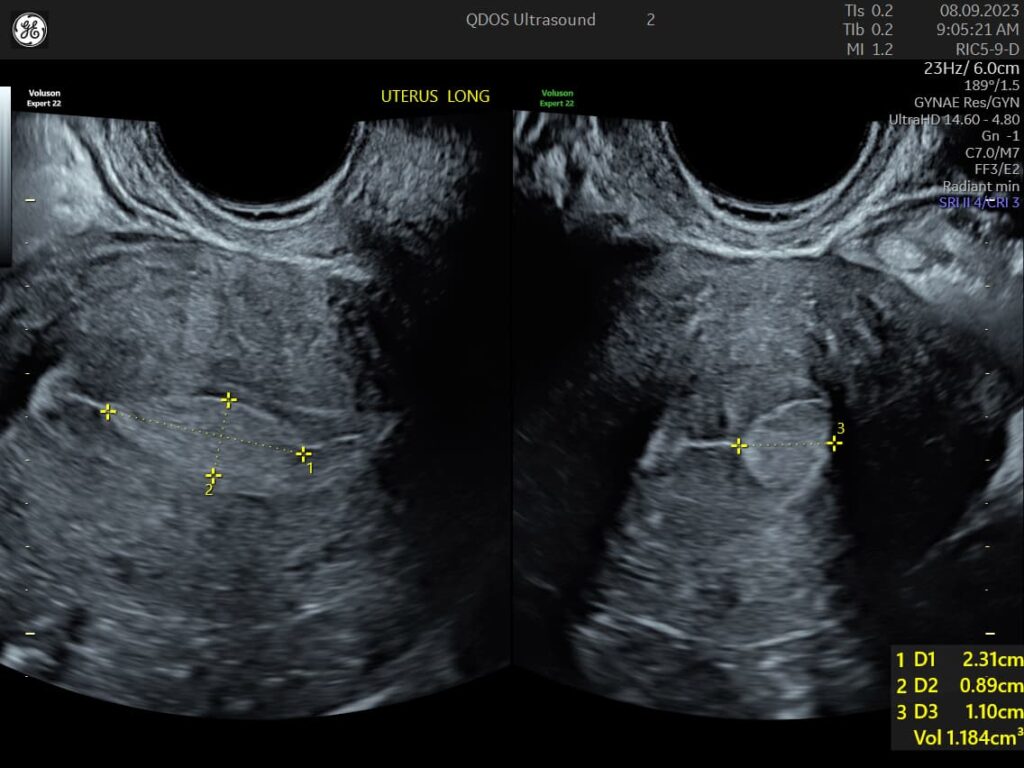

Painful or heavy periods are common reasons for a gynaecology ultrasound. Conditions like fibroids, endometriosis, adenomyosis, uterine polyps, or abnormal thickening of the uterus lining may be responsible. Whilst endometriosis cannot be excluded by ultrasound, our team are specialists in looking for the recognisable ultrasound features of endometriosis.

Abnormal bleeding sometimes can be linked to several conditions visible on an ultrasound, such as polyps, fibroids, abnormal thickening of the uterus lining, or unusual ovarian activity. At QDOS Ultrasound, we specialise in detailed gynaecological imaging to recognise the difference between these abnormal findings, as well as to recognise variations of normal.